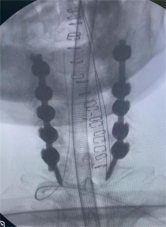

8. 机器人导航辅助下脊柱侧弯矫正技术

脊柱侧弯是一种复杂的脊柱三维畸形,其中以青少年特发性脊柱侧凸最常见。性爱视频

在浦口地区率先开展机器人导航辅助下脊柱侧弯矫正术,实现了脊柱侧弯手术准确、微创、智能化的突破,获得了良好的效果。还有老年人退变性侧弯,机器人亦可精准置入困难椎弓根螺钉,误差只有0.3mm。